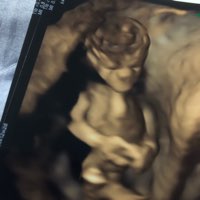

Bejbik

Załączniki

• 75DE46B6-7BB2-4A3E-A9D8-F4415FC57A04.jpeg

75DE46B6-7BB2-4A3E-A9D8-F4415FC57A04.jpeg

7,2 KB · Wyświetleń: 107